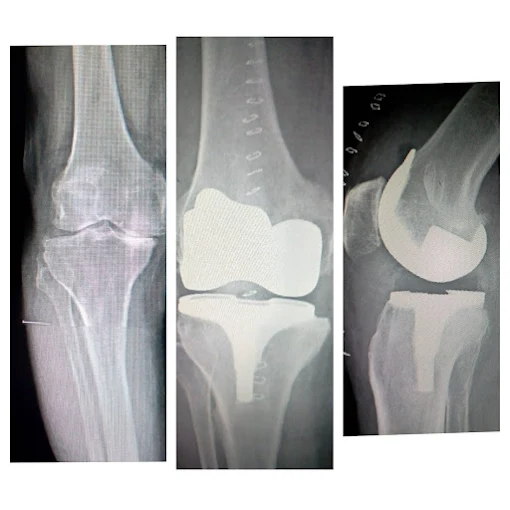

Joint Replacement

Advanced hip and knee replacement surgeries in Wakad, Pune

Hip & Knee Replacement

Comprehensive joint replacement solutions using modern implants

Robotic Knee Replacement Surgery

Yes, Dr. Sachin Sonawane is a highly experienced knee replacement surgeon wakad pune and hip replacement surgeon wakad pune, performing advanced joint replacement procedures at Wakad, Pune using modern implants to restore mobility and reduce chronic joint pain.